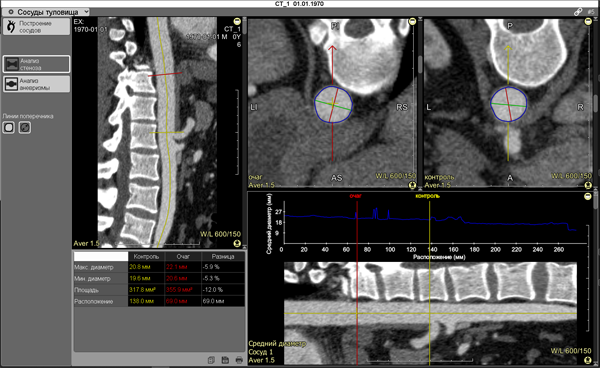

The screen will split into 5 panels:

1 - Arbitrary curvilinear projection with free rotation

2 - Cross-section of the stenosis zone

3 - Control cross-section

4 - Table of measurement results

5 - Vessel longitudinal view and the vessel lumen graph above it

The table (bottom left panel of the screen) displays the measurement results:

Maximum diameter

Minimum diameter

Cross-sectional area

Distance from the construction point

Difference between values (in percentage and mm)